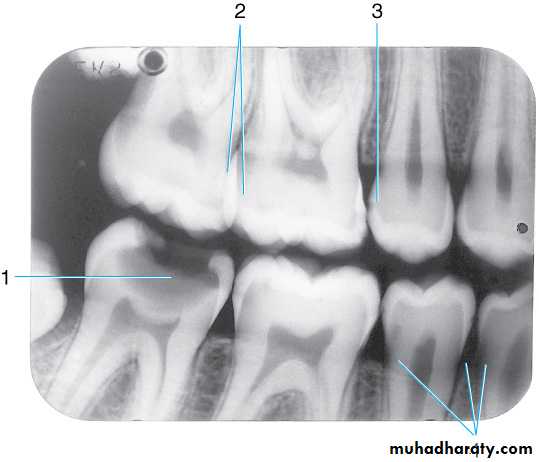

Radiograph of mandibular molar area. Shown are the

(1) Ext oblique ridge,(2) mylohyoid or internal oblique ridge,(3) mandibular canal and

(4) submandibular fossa